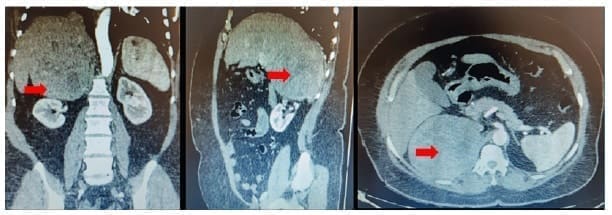

La tomografía computarizada de abdomen simple y contrastada confirmó la presencia de una masa solida adrenal derecha, de 11 x 10,5 x 10,7 cm, de densidad heterogénea, con áreas centrales hipodensas por necrosis, que desplazaba y con efecto compresivo sobre la vena cava y renal derecha, y en estrecha relación con la arteria renal derecha aproximadamente a 1,8 cm de su origen, compatible con carcinoma adrenal cortical (figura 2).

Figura 2. Tomografía computarizada de abdomen simple y contrastada con

evidencia de lesión tumoral en la glándula suprarrenal derecha.

Fuente: Hospital Universitario San Vicente Fundación